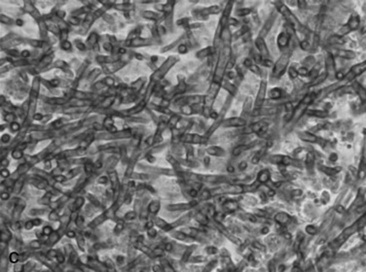

C. coronatus is a saprophytic fungus that causes granulomatous lesions of the upper respiratory tract in horses. Single to multiple granulomatous lesions in the nasal passages, trachea, or soft palate can be observed endoscopically (Fig. 31-19). Histologic appearance of conidiobolomycosis is similar to that of pythiosis and basidiobolomycosis. Hyphae of C. coronatus are thin-walled, highly septate, and irregularly branched (see Table 31-5).356 The lesions typically have large numbers of eosinophils and fewer macrophages, neutrophils, plasma cells, and lymphocytes surrounding hyphae. Definitive diagnosis is based on microbiologic culture, immunodiffusion, or PCR.357 Detection of serum antibodies by immunodiffusion is considered highly sensitive and specific354,358 and can be used to monitor response to treatment.358 A nested PCR Pythium assay has also been used to identify C. coronatus.359

image

Fig. 31-19 Endoscopic image of mycotic granulomas caused by Conidiobolus coronatus in the nasopharynx of a horse.

Conidiobolomycosis lesions can be treated with surgical excision, laser therapy, cryotherapy, or long-term administration of iodides or antifungals.342,354,357 Amphotericin B has been administered intralesionally or topically in combination with dimethyl sulfoxide (DMSO) to treat C. coronatus.342-345 It is important to remember that long-term therapy and reevaluation are essential, as recurrence can occur.345 Oral fluconazole was successful in treating two pregnant mares with nasal conidiobolomycosis.360 A vaccine using C. coronatus antigen from broth cultures was unsuccessful in treating seven horses with conidiobolomycosis.357